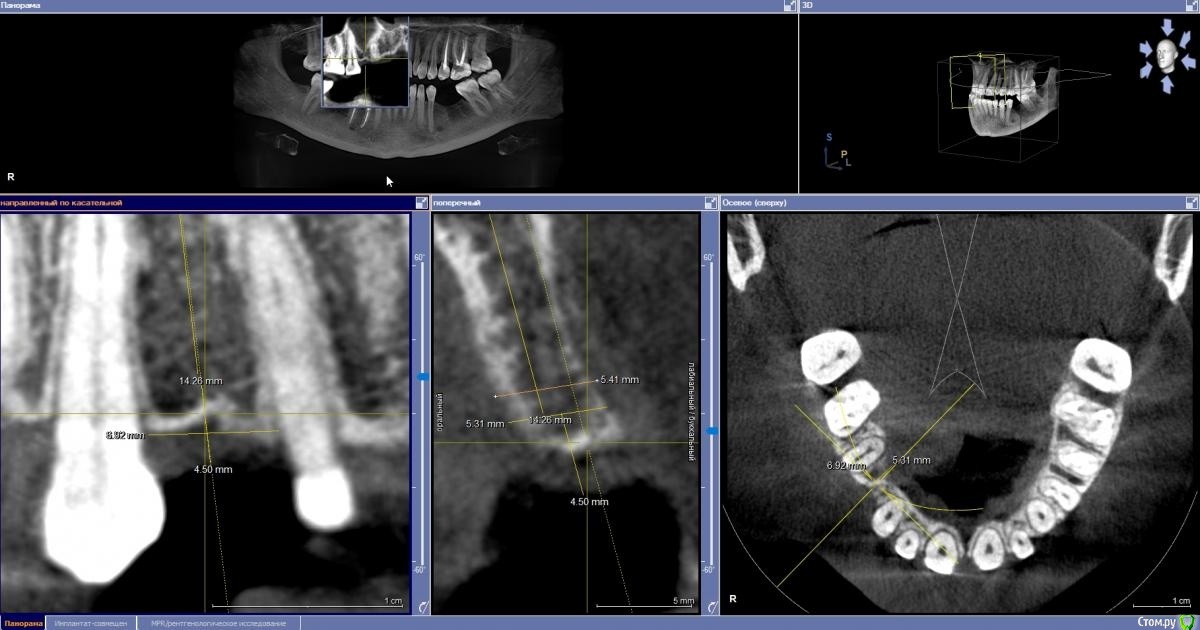

Fin Опубликовано 14 марта, 2021 Автор Поделиться Опубликовано 14 марта, 2021 (изменено) У Томаса в книжке описаны исследования, согласно которым главный фактор стабильности - биологическая ширина (которую он именует толщиной мягких тканей над имплантом). Он же утверждает, что достаточно покрытие платформы импланта только с 3 из 4 краев костным краем. Поэтому математика простая - вестибулоорально диаметр винта+1 мм, мезиодистально диаметр винта+2 ммВестибулоорально Вы имеете ввиду, вестибулярно отсутствует кость а орально 1 мм? Такие исследования там так не нашел видел только, что платформа может быть не покрыта ветибулярно только на 1 мм в глубину иначе есть возможность развития переимплнатита. Задался таким вопросом т.к. есть пациенты которым не хотел быпроводить НКР но условия близкик к минимальным значениям. Я сторонник классики, предпочитаю, чтоб имплантат был вестибуло-орально окружен 2 мм кости. Пути достижения - разные, от позиционирования ( согласовав, предварительно, расположение протетической платформы) , до костной пластики и редукции гребня. Все эти мысли - по поводу, нормальности остатка 1 мм кости, вряд ли устроят пациента через 3-4 года.Понимаю Вас, но не всегда получается обойтись редукцией либо она будет очень большой. Стоит ли всегда делать НКР в таких случаях для достижения заветных 2мм? П.С. Как считаете лучше поступить? В первом случае думаю может лучше обойтись импл 3,2(боюсь сломаться может) + навигация или все таки 3,5? Во втором случае планирую мост 2.4-2.6 хочу поставить 4х10 в обл. 2.4, прийдется убирать десну, т.к. боюсь что 3.5 может не выдержать. Изменено 14 марта, 2021 пользователем Fin Ссылка на комментарий

Irouil Опубликовано 14 марта, 2021 Поделиться Опубликовано 14 марта, 2021 Вестибулоорально Вы имеете ввиду, вестибулярно отсутствует кость а орально 1 мм? Такие исследования там так не нашел видел только, что платформа может быть не покрыта ветибулярно только на 1 мм в глубину иначе есть возможность развития переимплнатита.Эмм, а что еще может означать "платформа может быть не покрыта вестибулярно" как не "вестибулярно отсутствует кость"? Ну и не всегда вестибулярно, если на то пошло.П.С. Как считаете лучше поступить? В первом случае думаю может лучше обойтись импл 3,2(боюсь сломаться может) + навигация или все таки 3,5? Во втором случае планирую мост 2.4-2.6 хочу поставить 4х10 в обл. 2.4, прийдется убирать десну, т.к. боюсь что 3.5 может не выдержать.В первом случае 3,5-4, во втором сместите винт оклюзальнее, там где-то 1,5 мм перезаглублено, ортопедию планируйте адекватную заглублению Ссылка на комментарий

Fin Опубликовано 14 марта, 2021 Автор Поделиться Опубликовано 14 марта, 2021 Эмм, а что еще может означать "платформа может быть не покрыта вестибулярно" как не "вестибулярно отсутствует кость"? Ну и не всегда вестибулярно, если на то пошло.В первом случае 3,5-4, во втором сместите винт оклюзальнее, там где-то 1,5 мм перезаглублено, ортопедию планируйте адекватную заглублениюПонял Вас. Видимо затупил немного. В первом случае 4 мм с веститбулярной стороны вообще не будет, мне кажется это нот гуд. Во втором случае смещение на 1.5 мм приведет к отсутствию кости вокруг платформы, думаю проще убрать немного десны и получить подлиннее коронку.П.С. объясните пожалуйста Ваше мнение по поводу 4мм имплант в 5.2 мм кости, это как раз то что я и хочу понять, реально ли без НКР или нет? Ссылка на комментарий

Irouil Опубликовано 14 марта, 2021 Поделиться Опубликовано 14 марта, 2021 В первом случае 4 мм с веститбулярной стороны вообще не будет, мне кажется это нот гуд.Я бы взял винт 3.5, конечно, но конический имплант 4мм + конденсер тут тоже нормально войдёт. Единственное ограничение - ангуляция, надо смотреть куда будет выходить шахта импланта. Платформу сместить ближе к небной стенке.Во втором случае смещение на 1.5 мм приведет к отсутствию кости вокруг платформы, думаю проще убрать немного десны и получить подлиннее коронку. Вокруг платформы? Я там вижу отсутствие только с небной стороны. Может, конечно, не 1.5, а всего 1 мм - надо замерять, но ориентир понятен.П.С. объясните пожалуйста Ваше мнение по поводу 4мм имплант в 5.2 мм кости, это как раз то что я и хочу понять, реально ли без НКР или нет?Так я же именно свое мнение и объяснил выше) 4 в 5.2 нормально, на мой взгляд (при условии расширения гребня и/или сужения тела импланта в апикальном направлении), но обязательно требует соблюдения БШ, а на верхней челюсти приветствуется конденсация. Ссылка на комментарий